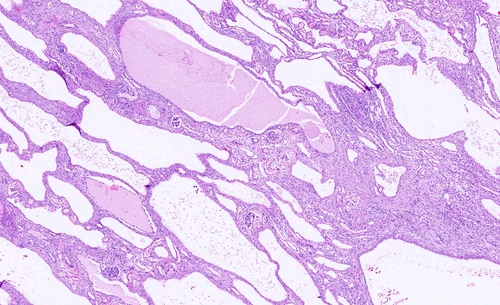

La malattia policistica renale autosomica dominante (autosomal dominant polycystic kidney disease, ADPKD), che negli adulti rappresenta la quarta causa di insufficienza renale, è una patologia congenita a trasmissione autosomica dominante (da cui il nome) causata da mutazioni nei geni PKD1 o PKD2 ed è principalmente caratterizzata dalla formazione di cisti a carico dei diversi segmenti del nefrone, con progressivo sovvertimento dell’architettura del parenchima renale e conseguente declino della funzione d’organo.

La malattia policistica renale autosomica dominante comporta un carico di malattia notevole su chi ne è colpito: entrambi i reni, talvolta fin dall’età dello sviluppo, sono interessati da un processo di formazione ed accrescimento di multiple cisti a partire dall’epitelio tubulare, che comporta un aumento volumetrico del 5-6% annuo di questi organi, fino al raggiungimento di volumi di occupazione notevoli. Le cisti possono andare incontro a diverse tipologie di complicanze ed essere causa di dolore ricorrente (più frequentemente in sede lombare) provocato da episodi di sanguinamento al loro interno e/o infezione; inoltre sono frequenti gli episodi di nefrolitiasi e di macroematuria.

Col tempo il danno meccanico si associa a quello flogistico e a quello legato ai processi riparativi, con il risultato di un precoce deterioramento della funzione renale che diviene solitamente evidenziabile agli esami di laboratorio a partire dalla V decade, cioè nel momento in cui le capacità di compenso funzionale dei reni iniziano ad esaurirsi.

La diagnosi di sospetto nasce solitamente dalla storia familiare di malattia del paziente e viene confermata con l’esecuzione di un’ecografia dell’addome, che evidenzia la presenza di cisti renali multiple in organi aumentati di volume. Frequente è anche il riscontro di formazioni cistiche a carico del parenchima epatico. In altri casi il sospetto diagnostico può nascere da una storia di ematuria ricorrente, soprattutto in un paziente iperteso o con storia di lombalgia frequente. Più raramente si tratta di una diagnosi incidentale in occasione dell’esecuzione di un’ecografia addominale per altri motivi in cui si riscontrino multiple cisti renali e/o epatiche. È importante precisare che il riscontro ecografico di cisti renali non è condizione sufficiente di per sé a porre diagnosi di malattia policistica renale autosomica dominante poiché cisti semplici, in numero limitato, possono formarsi durante l’arco della vita, specie dalla IV decade in poi, e il loro numero può aumentare nell’età avanzata. Esistono criteri ecografici specifici per la diagnosi di ADPKD in pazienti con storia familiare positiva.